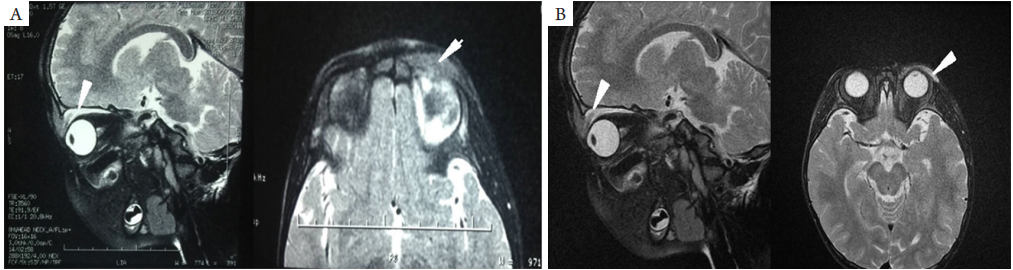

图 1 眼眶 MRI 图像

Figure 1 Orbital magnetic resonance imaging

(A) 治疗前图像示左眼上睑软组织肿胀 ( 箭头所指 ),T2 呈高信号,左眼上直肌轻度增粗 ( 箭头所指 ),左侧泪腺较对侧增大;(B) 治疗后图像示左眼上直肌、左上眼睑及邻近软组织肿胀较入院时明显减轻 ( 箭头所指 ),呈长T1 长T2 信号。

(A) Pretreatment images showed soft tissue swelling of the upper eyelid of the left eye (indicated by arrow) on T2, mild thickening of the superior rectus muscle of the left eye (indicated by arrow), and enlargement of the left lacrimal gland; (B) Post-treatment images showed that the swelling of the left eye rectus muscle, left upper eyelid and soft tissues was a brisk clinical improvement compared with that at admission (indicated by arrows), showing long T1 and long T2 signals.

患儿,男, 3岁,因“左眼红肿12 d ”就诊。患儿就诊前1个月有感冒病史。2019年4月1 8日,患者出现左眼眼睑红肿,当地医院诊断“左眼睑炎”,予以头孢咪唑2 g每天1次、地塞米松磷酸钠5 mg每天2次静脉滴注2 d后,症状好转后反复。2019年4月29日再次于外院眼科门诊就诊,眼眶及视神经MRI显示:1)左眼上睑软组织肿胀,考虑炎性改变;2 )左眼上直肌轻度增粗;左侧泪腺较对侧增大(图1A)。建议活检明确诊断。患者家属拒绝活检。同日就诊暨南大学附属第一医院眼科门诊,眼部检查示:左眼眼睑红肿(++++),眼眶鼻侧可触及约黄豆大小硬结,界不清,质地中等,压痛(?),伴上睑下垂,遮盖角膜下缘(图2)。双眼眼位正,左眼眼球外转轻度受限。辅助检查:降钙素原>0.1 ng/mL,循环免疫复合物>110,CRP+风湿4项+免疫球蛋白+补体7项未见异常。结合患者眼部症状及影像学资料,诊断为“左眼特发性眼眶炎性假瘤”。血液内科会诊排除血液系统恶性疾病后,予以全身静滴地塞米松磷酸钠2.5 mg[0.25 mg/(kg·qd)],局部抗炎、护胃等对症治疗。48 h后患者左眼下睑可自行抬高距离角膜下缘约2 mm。治疗6 d后复查,降钙素原<0.1 ng/mL,血常规:WBC<10×1 09/ L,生化八项未见异常。眼部B超(2019年5月5日;图3 ):左眼内上方见1.7 cm×1.9 cm占位病变,边界清,形态欠规则,内回声欠均匀,周边可见少许血流信号;右眼未见明显异常。眼眶及视神经MRI(2019年5月9日;图1B):左眼上直肌、左上眼睑及邻近软组织肿胀较入院时明显好转,呈长T 1、长T 2信号。住院治疗9 d后,患者左眼眼睑炎性症状好转,呈中度上睑下垂,眼眶鼻侧硬结较入院减小,双眼眼位正,左眼眼球运动正常,出院后继续口服泼尼松15 mg[1.5 mg/(kg·qd)],维持1周后每周逐渐减1.25 mg直至停药。患儿出院1周后复诊,查体左眼眼眶鼻侧未触及明显硬结,上睑下垂症状消失,双侧睑裂对称。